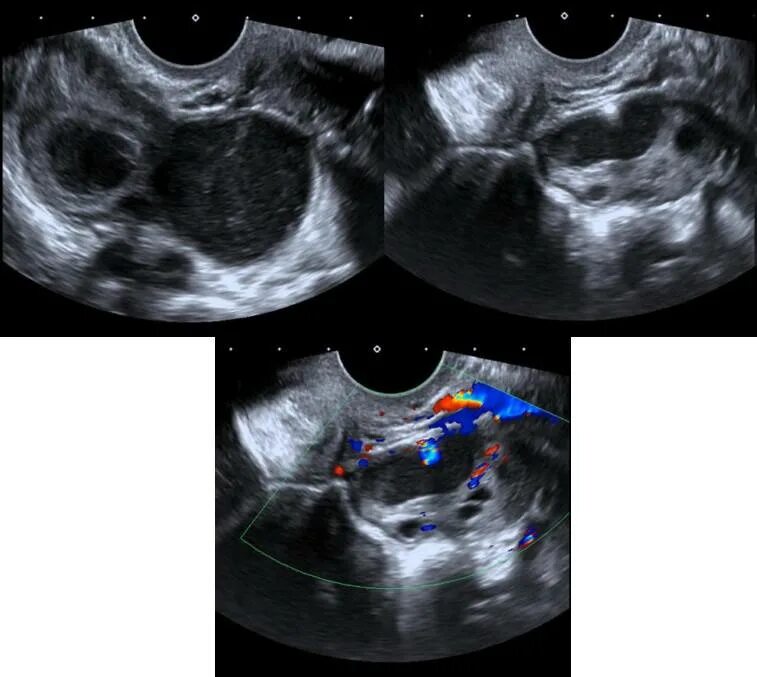

Как выглядит яичник